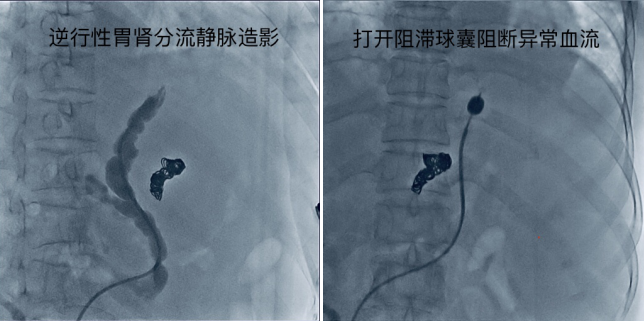

患者肝硬化、门脉高压、食管胃底静脉重度曲张数年,此前就因反复多次消化道大出血辗转于多家医院,接受过多次内科及内镜下止血治疗,但出血仍然反复发生,入住我院消化内一科,经介入、肝胆、消化多科室反复讨论,确定介入微创方式进行出血静脉的硬化闭塞治疗。手术由介入放射科陈思攀、颜昭勇医师完成,通过静脉逆行性造影探查,明确病变的食管胃底静脉后,在透视下向静脉腔内注入血管硬化剂,短期内即达到了硬化闭塞血管,阻断异常血流的目的,通过术中造影及临床观察,患者病变静脉闭塞治疗满意,术后恢复良好,在院观察期间未再出血。

球囊阻滞下逆行性食管胃底静脉栓塞术(BRTO),是经股静脉或颈静脉穿刺,在患者异常分流道中置入阻滞球囊,堵塞异常血流后,注入硬化剂,使曲张的食管-胃底静脉腔硬化闭塞,从而达到断血、止血之目的。 该治疗常用于存在自发性分流道的食管-胃底静脉曲张,尤其适用于内镜治疗后反复出血的顽固性食管-胃底静脉曲张破裂出血患者。